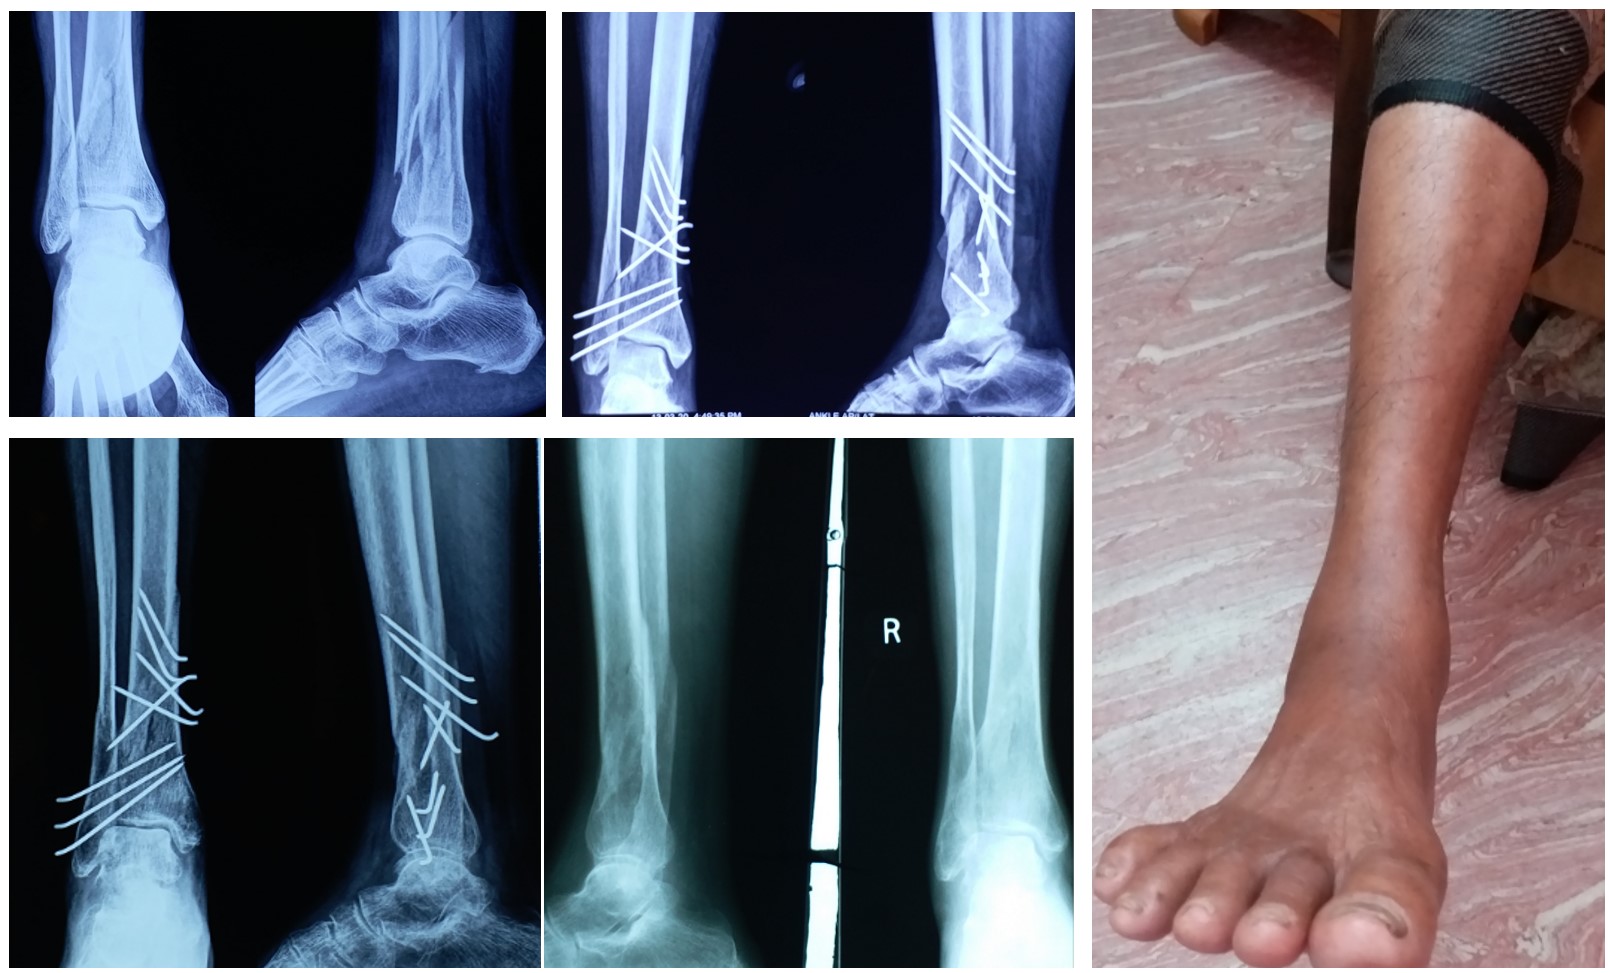

Distal 3rd Leg